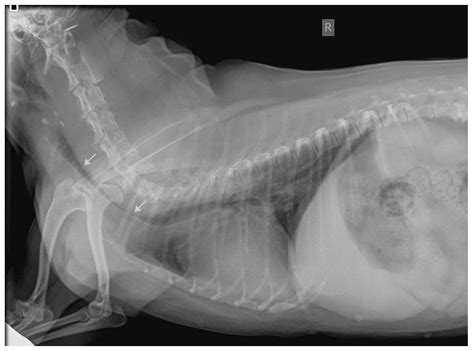

Yet diagnostic gaps persist. Standard imaging often misses dynamic airway collapse, and owner-reported timelines lack precision. Emerging tools like real-time endoscopic videography offer clarity—capturing the exact moment of mucosal vibration—but remain inaccessible to most. Without widespread adoption, many cases go undiagnosed, masking a quiet but growing public health concern for pet well-being.